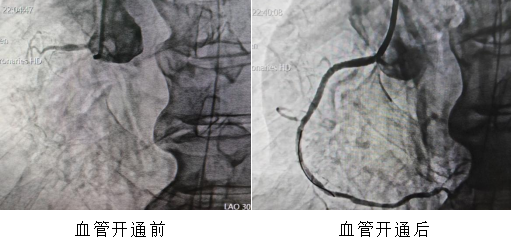

这不是一组普通的时间记录,而是一个真实的、发生在海南医科大学第一附属医院导管室的急救故事——前不久的一天,12小时内,通过胸痛中心绿色通道,5位急性心肌梗死患者,5台急诊经皮冠状动脉介入治疗(PCI)手术,全部成功。

22分钟、70分钟、36分钟、18分钟、12分钟——这是5颗心脏血管从“断流”到“复流”,解除堵塞病变的时间。如此高密度、高效率的连续急救,绝非偶然,它是我院胸痛中心标准化、流程化救治能力的集中体现。它的背后,是院前院内无缝联动,120急救车上已完成的心电图传输与初步诊断,患者“未到,信息已到”,导管室提前启动;是术前早已启动的医院胸痛中心绿色通道——患者到我院后可绕行ccu和(或)急诊科,直接进入导管室,最大限度压缩术前准备时间;更是心内科、急诊科、心电图室、导管室护理团队等多学科团队的无缝咬合,高效协作。这是急诊急救体系建设的力量。